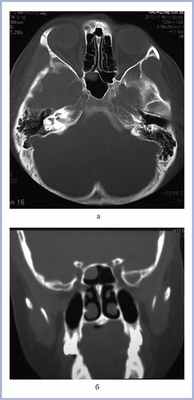

В апреле 2010 г. в связи с затянувшейся острой респираторной инфекцией пациентке была назначена КТ околоносовых пазух; подтверждено наличие кистоподобного образования, которое увеличивалось в размерах (рис. 2, а, б).

Рис. 2. Компьютерная томограмма околоносовых пазух больной Г.

После излечения от острой респираторной инфекции пациентка в течение 3 лет чувствовала себя здоровой. В феврале 2013 г. появились интенсивные головные боли, локализующиеся позади правой орбиты. Больная вынуждена была вызвать скорую помощь, вводились анальгетики, которые временно облегчили состояние. На К.Т. от 10.11.13 выявлено заполнение правой клиновидной пазухи патологическим секретом, в ее переднем отделе наблюдается образование округлой формы (рис. 3).